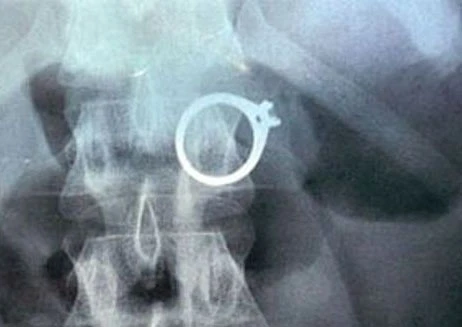

| Để tẩu tán số vàng vừa trộm cắp để thoát tội, Lanh đã nuốt một chiếc nhẫn vàng và hai vòng đeo tai vào bụng. Ảnh: Petrotimes |

Tại cơ quan công an, Lanh đã thừa nhận hành vi trộm cắp tài sản của mình. Lanh khai báo thêm, với mục đích tẩu tán số vàng vừa trộm cắp để thoát tội, Lanh đã nuốt một chiếc nhẫn vàng và hai vòng đeo tai vào bụng.

Để xác minh lời khai, công an đã đưa Lanh đi chụp X-quang, kết quả cho thấy có phát hiện vàng ở dạ dày Lanh. Vụ việc đang được cơ quan chức năng điều tra, làm rõ.